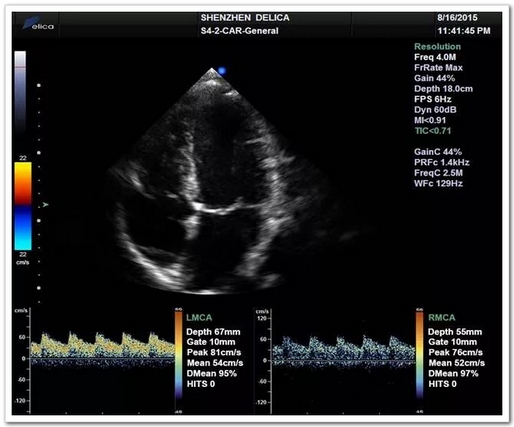

心臟超聲與顱內(nèi)血流同屏同步顯示

全球唯一!